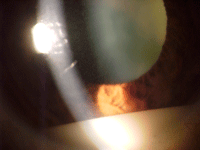

En la exploración biomicroscópica de la endoftalmitis hallaremos tyndall en cámara anterior, que puede ser proteico

(flare), celular (

Figura 1) y habitualmente es mixto.

Figura 1. Imagen en la lámpara de hedidura del flare celular en cámara anterior.